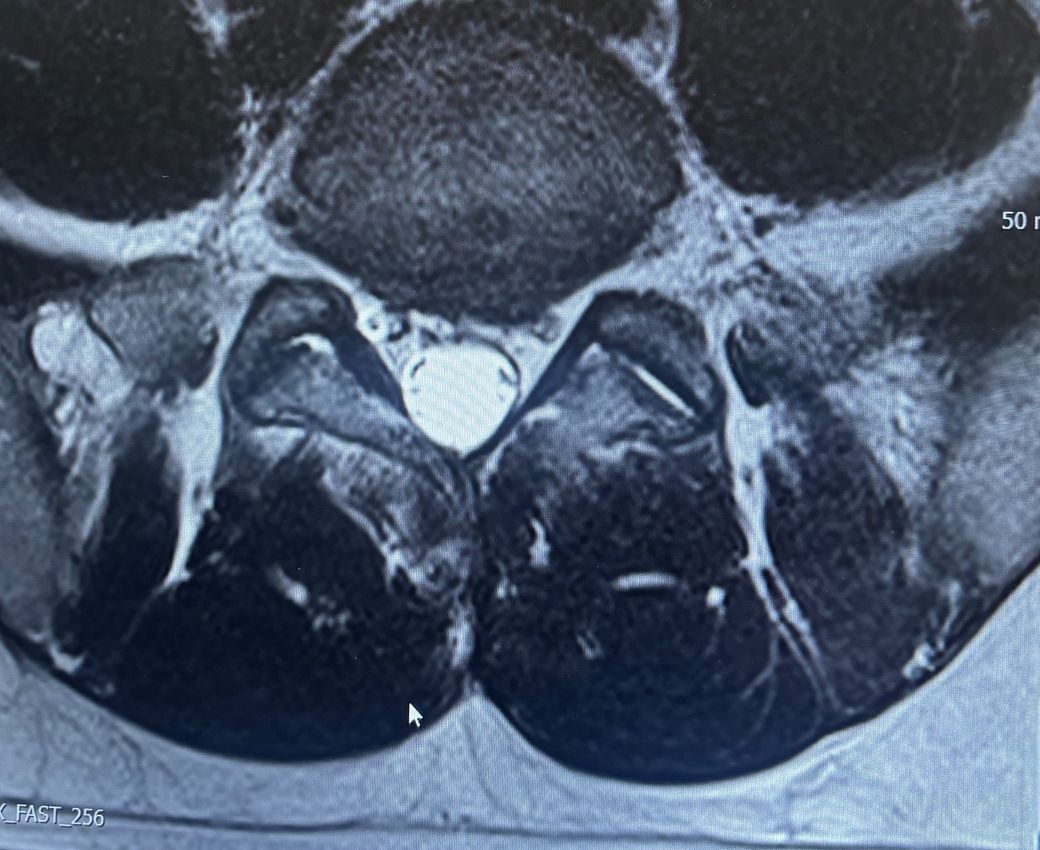

허리디스크 추간판 탈출증 좌측하지 방사통

군대 현부심 할려고하는데 가능할까요 왼쪽 허벅지 뒤 땡김이랑 발목이 잘 안올라가요 누워있으면 허리가 뜨거워지면서 쑤시고 많이 저려요.. 걷는것도 쩔뚝 거리면서 걸려요 허리쓰는 활동이 많아서 도 심해질까 걱정되네요..

디스크 진단만으로는 등급판정 시 4급이 나올 가능성은 적고, 올려주신 MRI나 신경증상 및 기능장애 여부들이 증요합니다.